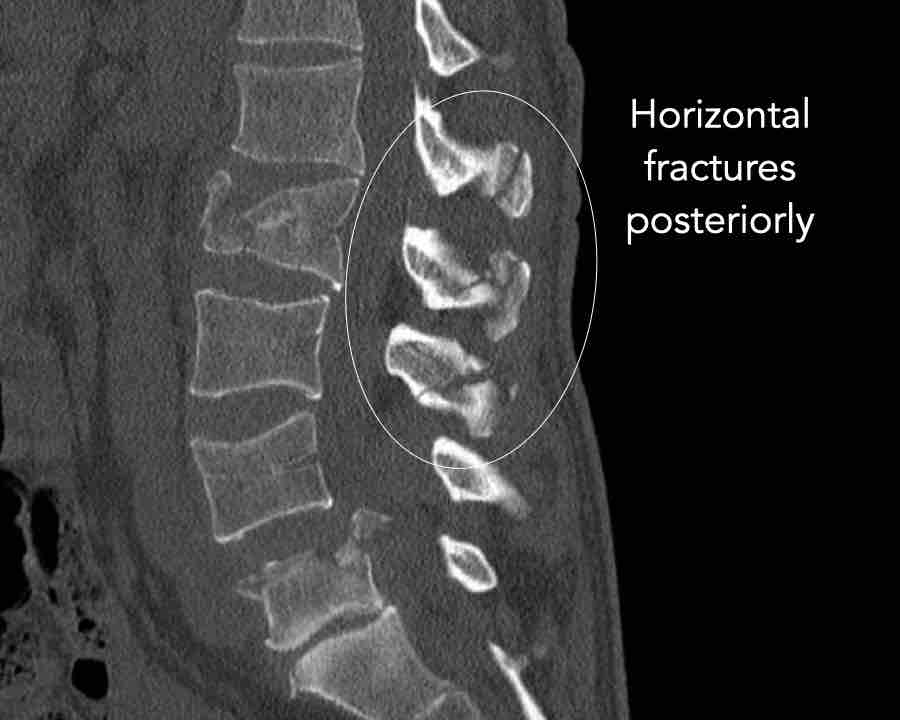

Findings

- No dislocation ( no C type).

- Mainly horizontal fractures of spinous processus at multiple levels (B-type).

- Split fracture L2 (type A2).

Conclusion

Injury type B2 + A2 at level L2.